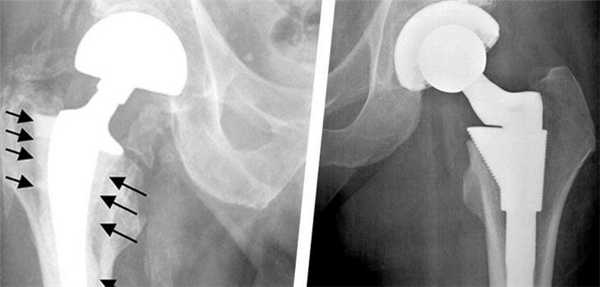

Дислокация бедренного компонента на рентгене.

Стрелками указаны зоны инфекционного воспаления, именно так они выглядят на рентгене.

Это – нарушение целостности бедренной кости в зоне ножки при нестабильном и стабильном протезе, возникающее интраоперационно или в любой момент после операции (через несколько дней, месяцев или лет). Переломы чаще происходят по причине сниженной плотности костных тканей, но могут быть следствием некомпетентно произведенной разработки костного канала перед установкой искусственного сочленения, неверно выбранного способа фиксации. Терапия в зависимости от вида и тяжести повреждения заключается в использовании одного из методов остеосинтеза. Ножку, если на то заменяют на более подходящую по конфигурации.

Разрушение импланта происходит очень редко.